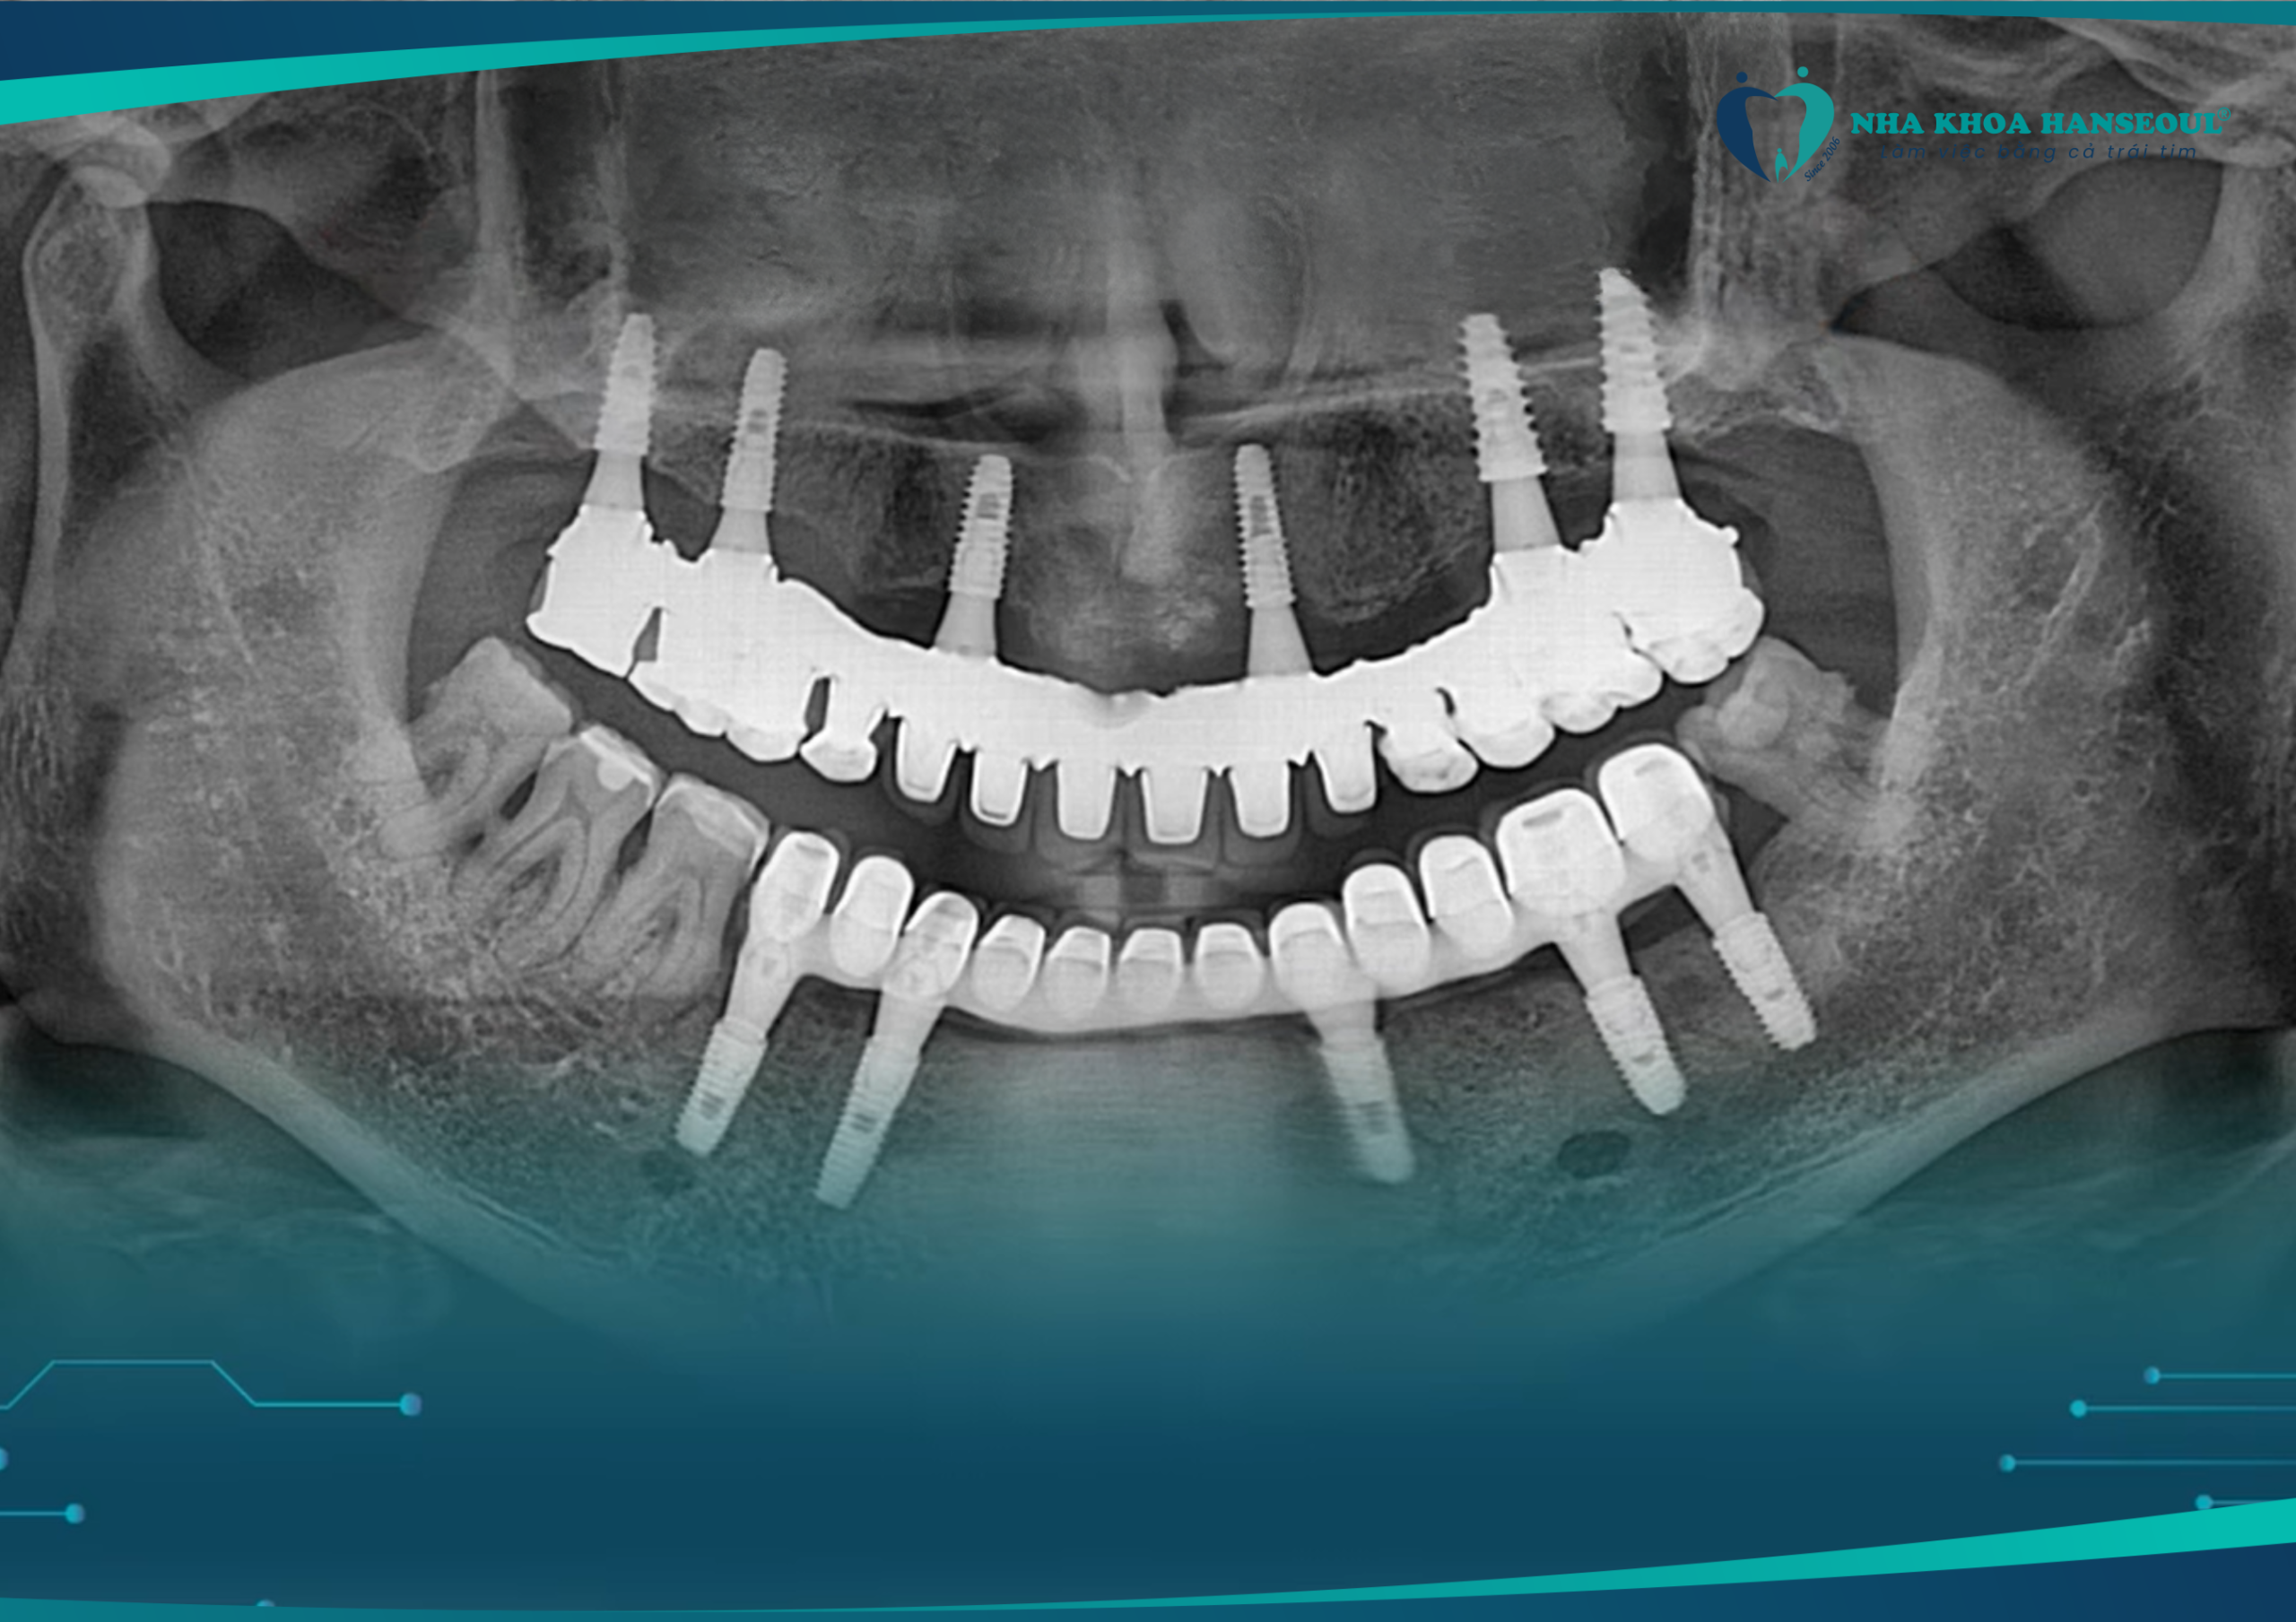

Kết quả chụp phim kiểm tra sau 8 năm cấy toàn hàm trên

Sau gần 10 năm, kết quả vượt ngoài mong đợi: “xương không tiêu, không viêm nhiễm, chức năng nhai chắc khỏe như răng thật”. Nhờ công nghệ Hansafe độc quyền, mỗi ca cấy ghép implant tại Hanseoul đều đảm bảo an toàn, chính xác và hiệu quả lâu dài.